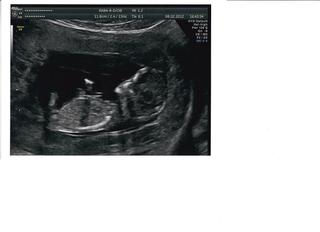

Idem na vás naprskať trochu tehu bacilov. Dnes som bola na KO, všetko je v pohode, mimčo na mňa mávalo. Minulý týždeň sme mali NT screening...Bolo to naozaj super vidieť mimino na takom kvalitnom utz. Mimi najprv spalo, ale ako doktorka začala jazdiť hore dole sondou, tak sa zobudilo a začalo sa strašne vrtieť, že ho skoro nemohla zmerať 🙂. Pravdepodobnost na vadu nam vysla 1:50 000 a doktorka na zaver skonstatovala, že by chcela na utz vidieť samé také zdravé miminá, ako je to naše...Prikladám fotečku.